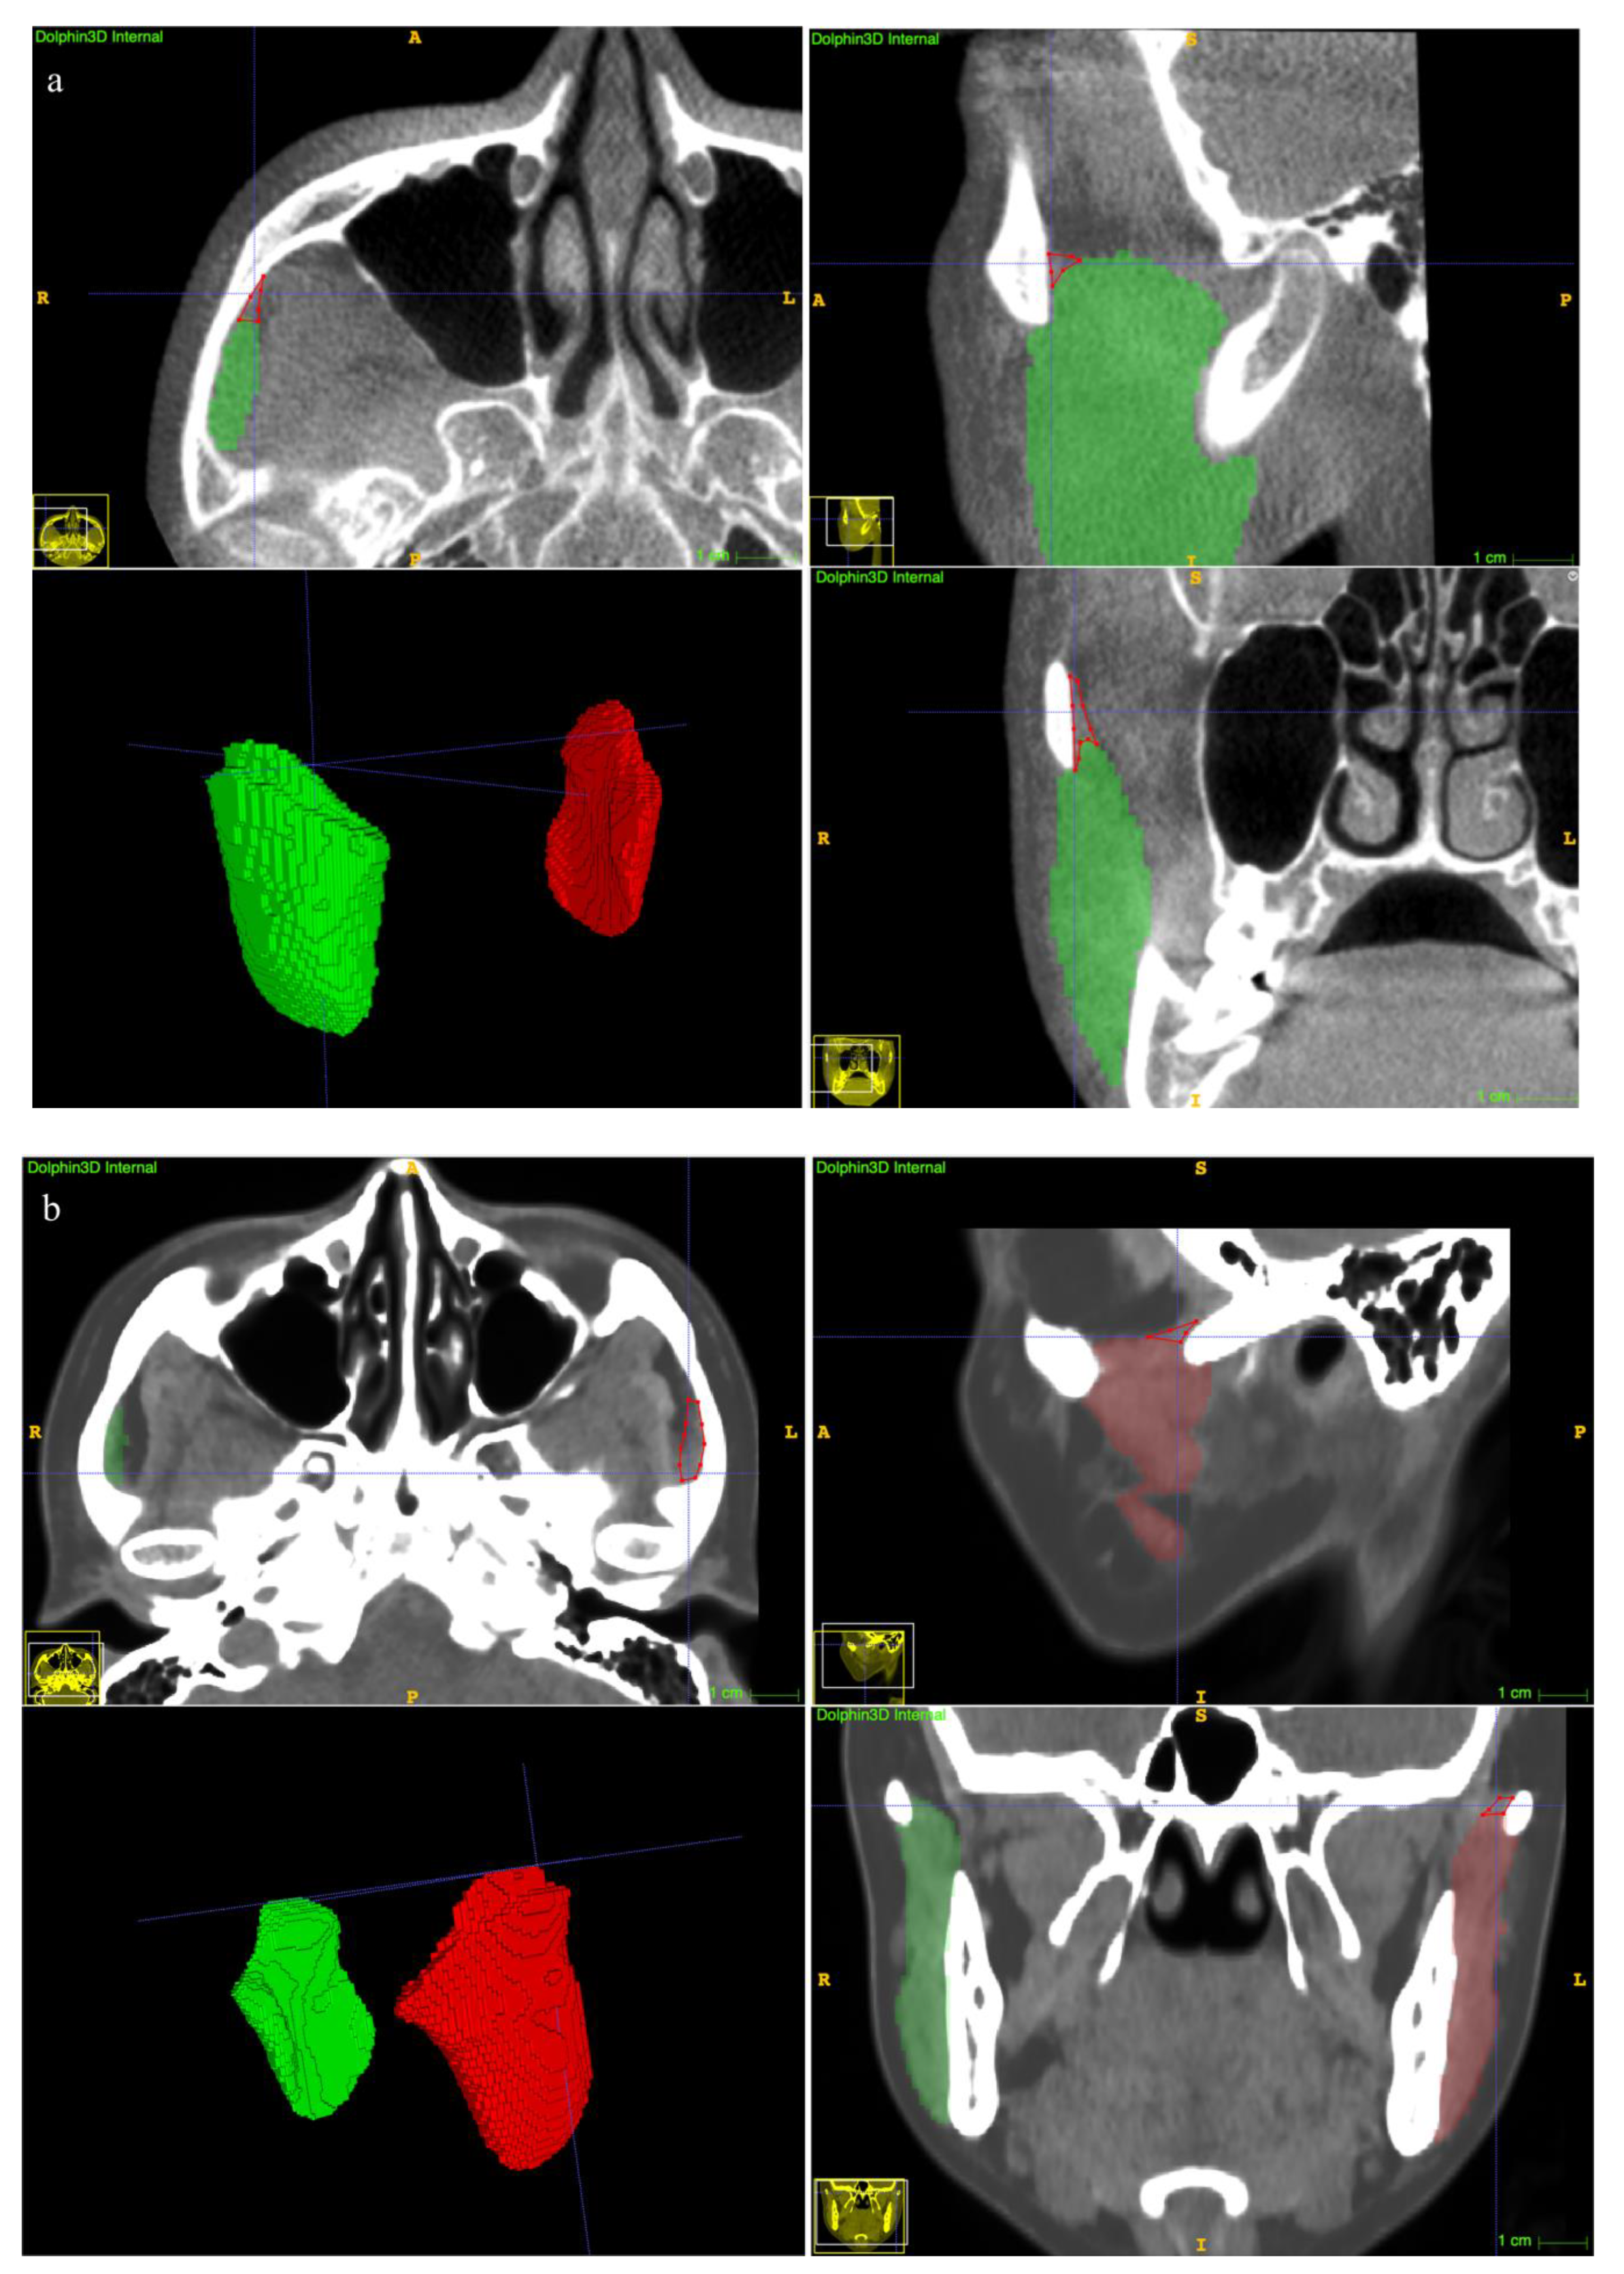

The clinical suitability results are summarized in Table 5. The manual revision was mainly focused on the superior extents (examples depicted in Figure 7a,b). A mean revision fraction of 0.52 ± 0.44% was needed for both CBCT and CT auto-segmentations, and the revision fraction ranged from 0.25% to 0.72% for each side of the MM. The mean DSCMean was 99.84 ± 0.14%, and the mean aHD was 0.92 ± 0.88 mm. SD, standard deviation.

Figure 7.

Examples of undersegmentation of the automatic model on the superior extent of the MM. The red polygon shows the undersegmented area. (a) CBCT segmentation results. (b) CT segmentation results.

With regard to the clinical suitability of the model, minor manual modifications for both the CBCT and CT auto-segmentation results were needed in this study (the mean manual revision fraction was 0.52 ± 0.44%, Table 2). A previous study reported a mean 22.86% of case revisions [18], suggesting an obvious improvement in terms of accuracy of our proposed method. Refinement was focused on the superior extents (Figure 7a,b). The explanation was that visualization of the MM superior ligament is poor [1], and the model threshold settings affect the identification results.